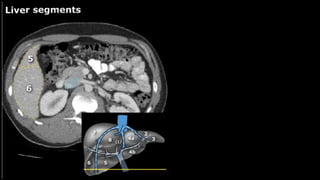

•Liver • A normalliver enhances homogeneously (irrespective of the scan phase). The liver receives about 80% of its blood through the portal vein (= nutrient-rich blood from the intestines). The remaining 20% is supplied by the hepatic artery. y is present, it is important to document its location. This may be crucial to any surgical options. Using the Couinaud classification, the liver is subdivided into eight individually functioning segments. Each segment has its own afferent hepatic artery and portal vein, and efferent hepatic vein and efferent bile ducts

Liver segments Radiopaedia.com1

• 5.

• 6.

• 7.

• 10.